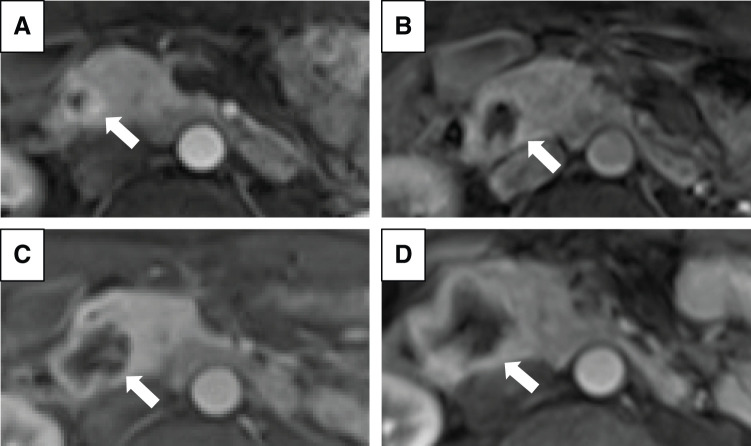

Case presentation: A male patient in his 30s had been diagnosed with VHL disease and had been followed for cerebellar and spinal hemangioblastomas, and renal cell carcinoma, for which he had undergone several tumor resections, radiation therapy, and a ventriculoperitoneal shunt. A pancreatic head tumor deemed to be a neuroendocrine tumor on imaging findings exhibited a gradual increase in size from 12 to 33 mm for the past 2 years, but it had been monitored due to his comorbidities and declining daily living activities. Severe anemia was detected during his regular outpatient visit, and an emergency esophagogastroduodenoscopy revealed a submucosal tumor near the duodenal papilla with ulceration and active bleeding, making endoscopic hemostasis challenging. Dynamic contrast-enhanced CT showed active bleeding from the pancreatic tumor. Subsequently, emergency angiography was performed via the superior mesenteric artery, successfully embolizing vessels supplied by the inferior pancreaticoduodenal artery to achieve hemostasis. Due to concerns about rebleeding, we performed pancreaticoduodenectomy 1 month after the emergency angiography, during which we awaited the improvement of the patient's overall condition. Microscopic findings of the tumor showed multinodular proliferation with hematoxylin-eosin staining, revealing cells with clear cytoplasm and abundant capillaries and dilated branching vessels within the nests. Immunohistochemical analysis demonstrated positivity for alpha-inhibin and S100, with partial positivity for carbonic anhydrase IX, leading to a diagnosis of pancreatic hemangioblastoma.